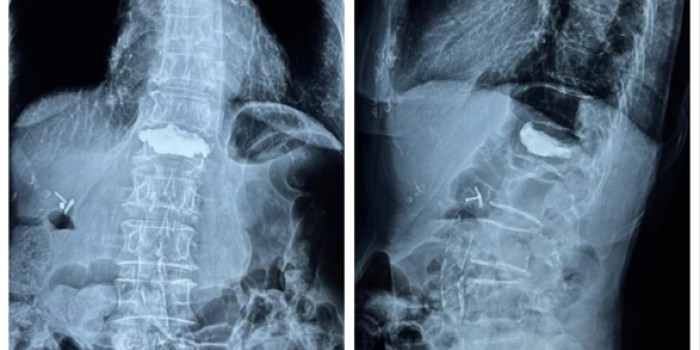

• Vertebroplasty / Kyphoplasty

• Osteoporosis / Osteoporotic fracture treatment